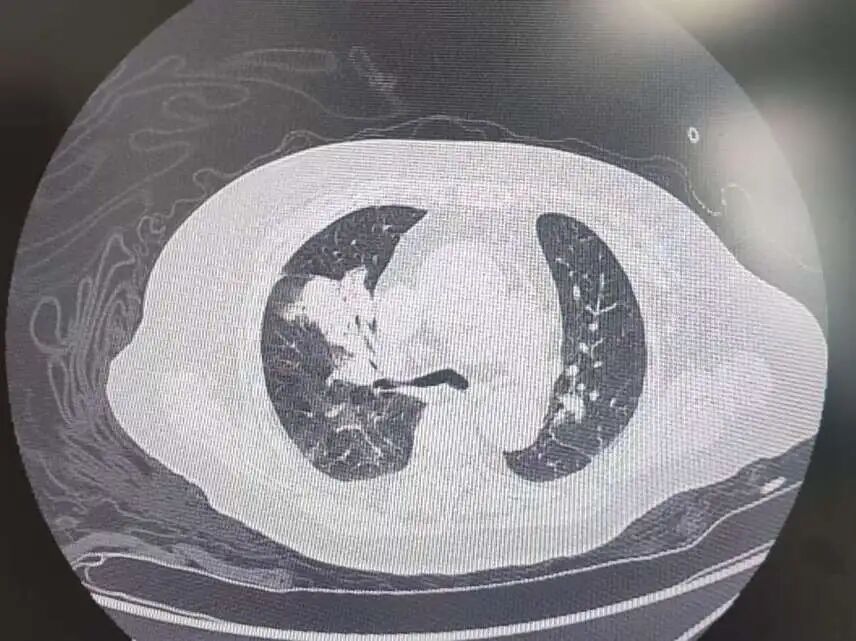

患者高血压病史7年,最高血压达190/100mmHg,2型糖尿病7年,控制不佳。发病前3天,意外摔伤致股骨颈骨折,后出现咳嗽、呼吸困难、胸痛等症状,被紧急送到我院急诊。完善相关检查后,明确诊断为中高危肺栓塞——这是一种足以危及生命的急症,病情进展迅速。

肺占位

为进一步精准救治,呼吸与危重症医学科宋刚主任带领团队对患者进行全面评估,结果令人揪心:肺血栓栓塞(中高危)、I型呼吸衰竭、肺占位性病变、急性冠脉综合征、急性肾功能不全、肝功能不全、脓毒症等多种疾病,且随机血糖高达31.68mmol/L,远超正常范围,生命体征岌岌可危。